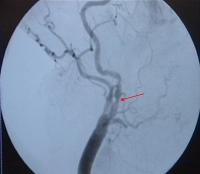

• hochgradiger Rezidivstenose (Filmbeispiel)

1. Protektions-Device: Jedes Sondierungsmanöver stellt per se ein Embolierisiko dar. Ohne Protektion sind zwei Sondierungen notwendig, mit Protektion mindestens drei. Da es sich im Filmbeispiel um eine narbige Re-Stenosierung handelt, wird auf ein Protektions-Device verzichtet.